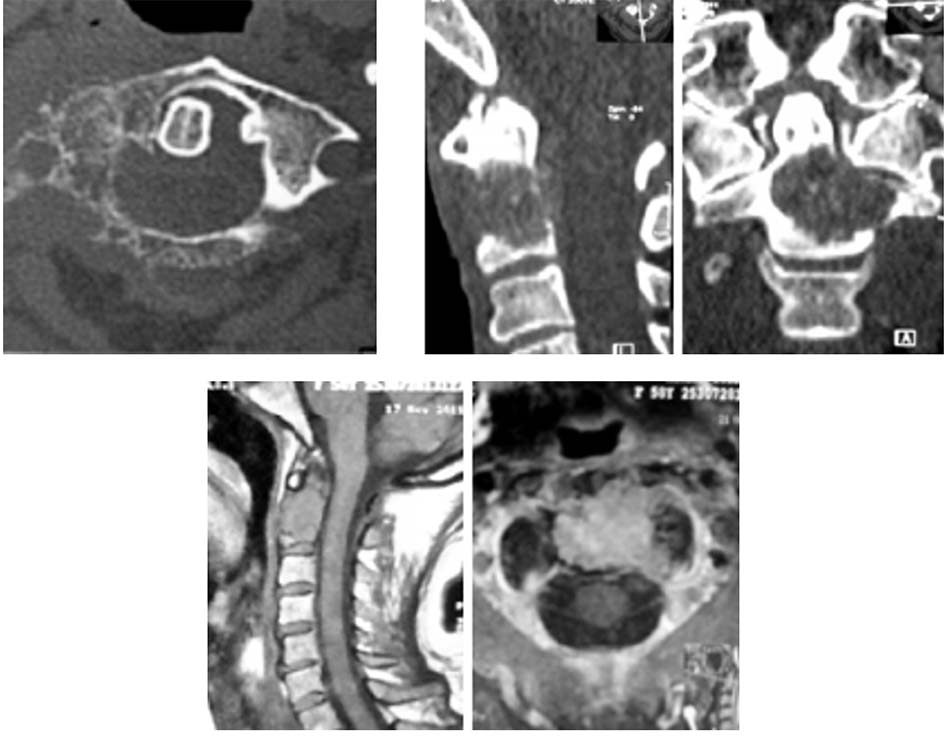

2.4.2. Các tổn thương do khối u tủy, ung thư hoặc di căn

Bên cạnh các tổn thương do chấn thương đã mô tả, các tổn thương do khối u phát triển tại chỗ hoặc do di căn vào các cấu trúc cột sống C1-C2 gây mất vững cũng thường gặp. Với các tổn thương này thường gây phá hủy cấu trúc xương cùng với phần mềm, vì vậy chỉ định nẹp cổ chẩm hay được chỉ định trong phẫu thuật nhằm làm vững cột sống sau phẫu thuật giải phóng chèn ép và lấy u.

2.4.3. Các tổn thương do viêm, lao, nấm

Bên cạnh các tổn thương phức hợp C1-C2 do chấn thương, bệnh lý, do khối u… chúng ta vẫn gặp các nguyên nhân khác như do viêm, lao hoặc nấm. Khi các tổn thương này lan tỏa gây phá hủy các cấu trúc giải phẫu làm mất vững cột sống cần phải chỉ định phẫu thuật. Tuy nhiên, việc lựa chọn đường mổ và phương pháp tái tạo đốt sống trong các tổn thương này cũng là một thách thức với các phẫu thuật viên cột sống. Bên cạnh lựa chọn phương pháp phẫu thuật thích hợp cho các tổn thương mất vững thì cần phải điều trị nguyên nhân gây nên các tổn thương này như viêm, lao hoặc nấm gây nên.